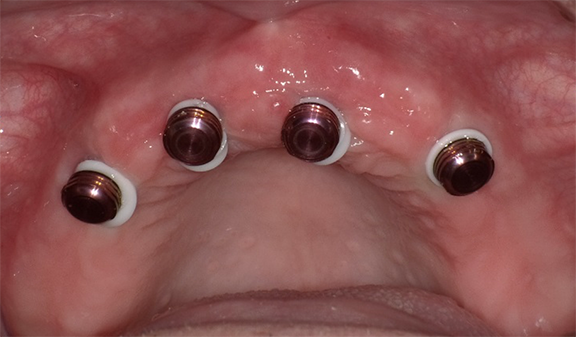

A fixed all-zirconia combination screw- and abutment-retained prosthesis was planned for the mandibular arch. Multiunit abutments were used to correct the angulation of the tilted distal implants54 and were torqued per the manufacturer specifications. Novel retentive abutments that would preclude the need for screws and cements were attached to the four anterior implants, rotated to ensure they were parallel to each other, and torqued per the manufacturer specifications (Figure 24).41

Fig 24. Multiunit abutments (gold) were attached to the distal-most implants, and novel abutments (pink) (LOCATOR F-Tx, Zest Dental Solutions) were attached to the four anterior implants.